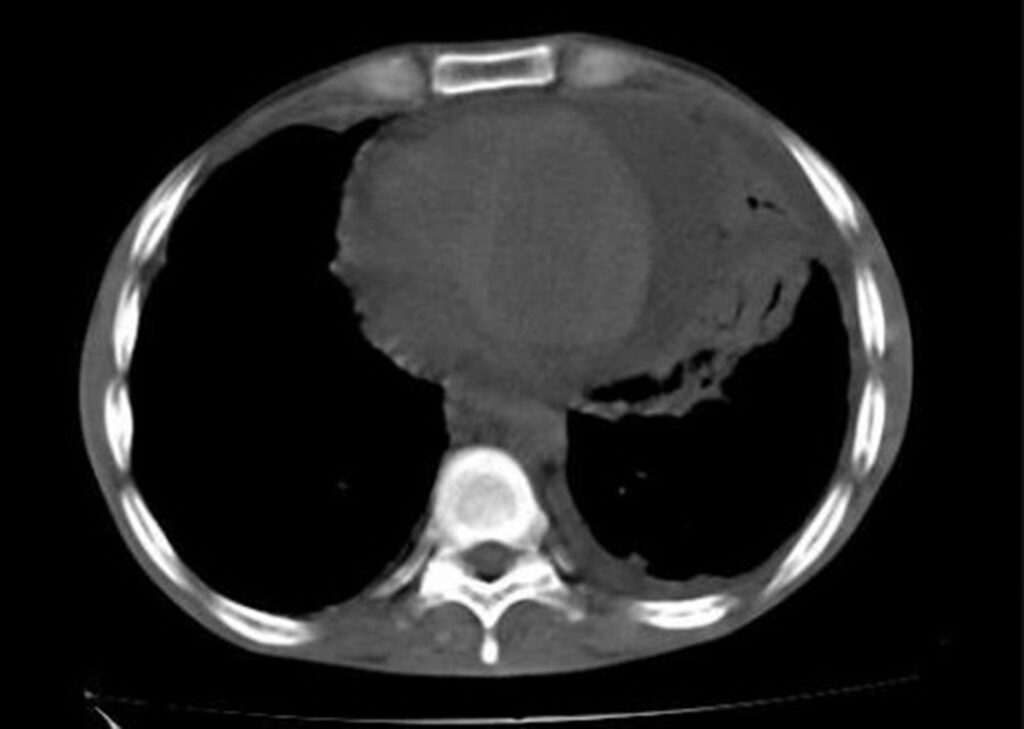

La radiografía de tórax es una herramienta diagnóstica que puede sugerir la presencia de un derrame pericárdico crónico a través de la observación de una silueta cardíaca aumentada con una configuración globular. Este hallazgo se debe a que, en situaciones crónicas, el líquido acumulado en el espacio pericárdico puede llevar a una expansión gradual del pericardio, resultando en un contorno cardíaco más prominente. Sin embargo, en casos agudos, la radiografía de tórax puede aparecer normal, ya que la acumulación rápida de líquido puede no ser suficiente para provocar cambios morfológicos evidentes en la silueta cardíaca.

La tomografía computarizada y la resonancia magnética también son útiles para demostrar la presencia de líquido pericárdico, así como para evaluar el engrosamiento del pericardio y cualquier lesión contigua asociada en el tórax. Estas técnicas de imagen ofrecen una visión más detallada de la anatomía del espacio pericárdico y pueden ayudar a identificar causas subyacentes de derrames.